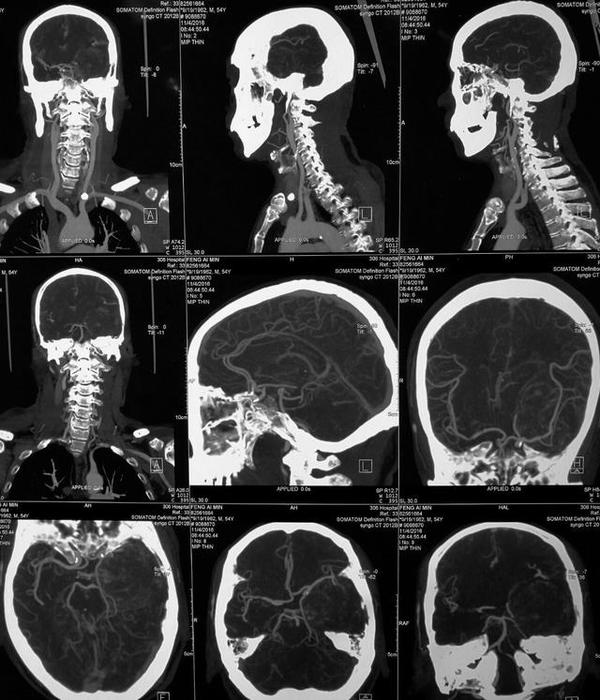

CT表现呈等密度、混杂密度、病灶边缘见小片高密度钙化。所有病灶边缘均光滑,与邻近脑实质分界清晰,无瘤周水肿,增强检查后均呈显著强化,强化均匀、部分不均匀,颈内动脉海绵窦段受压移位,部分病灶包绕血管,颈内动脉未见明显狭窄。CT骨窗上有中颅窝底、前床突及岩尖部等有骨质吸收,未见明显骨质增生。

有学者认为海绵窦海绵状血管瘤与雌激素、孕激素和促性腺激素的水平有关 。而Ohata等则认为这是颅内高血流状态和动脉收缩压升高所致。有文献报道部分患者有腺垂体功能减退的症状,与肿瘤向鞍内生长有关。海绵窦海绵状血管瘤的影像学特点为同时累及鞍旁和鞍内的单发大肿块,呈哑铃状,密度多均匀而少出血和钙化,其在CT扫描时呈等或稍高密度,瘤内常无钙化,可侵蚀颅骨,但一般不伴骨质增生。MRI扫描时T wI明显高信号和显著均质强化是其重要的诊断依据 ” 。